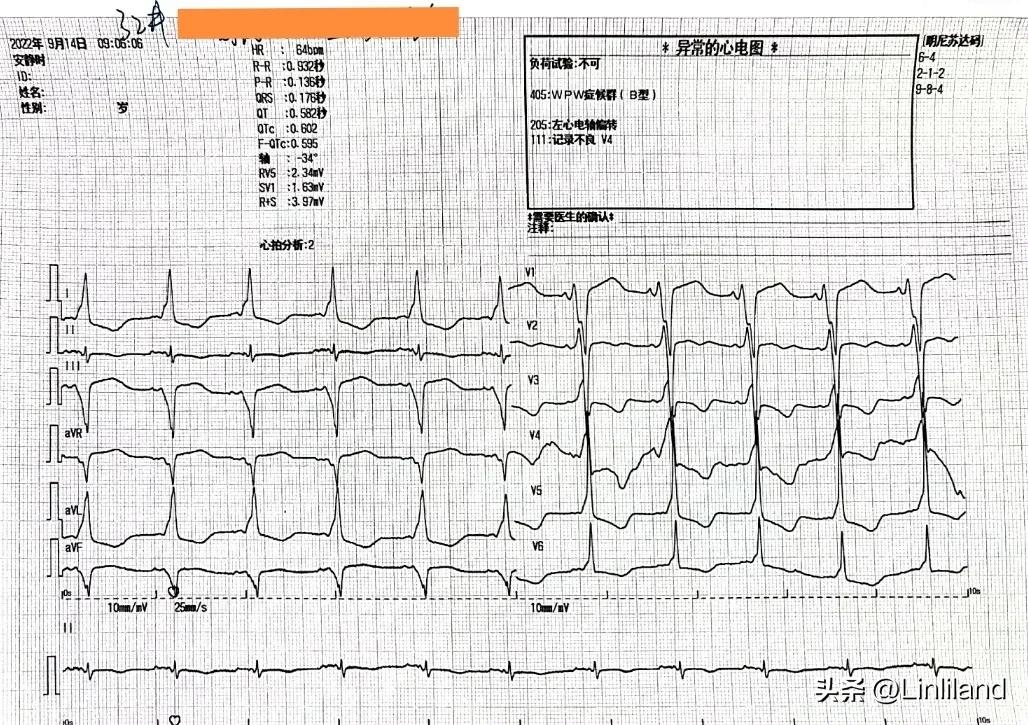

电复律后转为窦性心律,全导心电图示B型预激综合征

是的,患者就是预激综合征,根据心电图来看属于B型预激,旁道当位于心脏右侧,由体表心电图判断,患者的旁道应该为右后壁,如果行射频消融,旁道的位置应该不是太难做的部位。我们把这一好消息迅速告知电生理科医生,同时也把预激综合征的心电图发给他们。

至此,患者的诊断应该真相大白。部分预激综合征,尤其是B型预激综合征可并发房颤,而患者就属于这种情况,根据患者出现症状的时间,这一个多月的预激合并持续性房颤频频作祟,快速的心室率驱使心脏不停地跳动、作功、耗能,由此导致了一种被称为“ 心动过速型心肌病 ”的心脏疾患。此外,旁道的存在不仅导致过快的心室频率,而且,由旁道下传的激动导致心室左右室非同步收缩,也加剧了心功能不全的发生,近年来就有人提出过“预激性心肌病”的概念,将之归入心律失常型心肌病的范畴,尽管这种心肌病非常少见,但目前已引起人们的关注及重视。